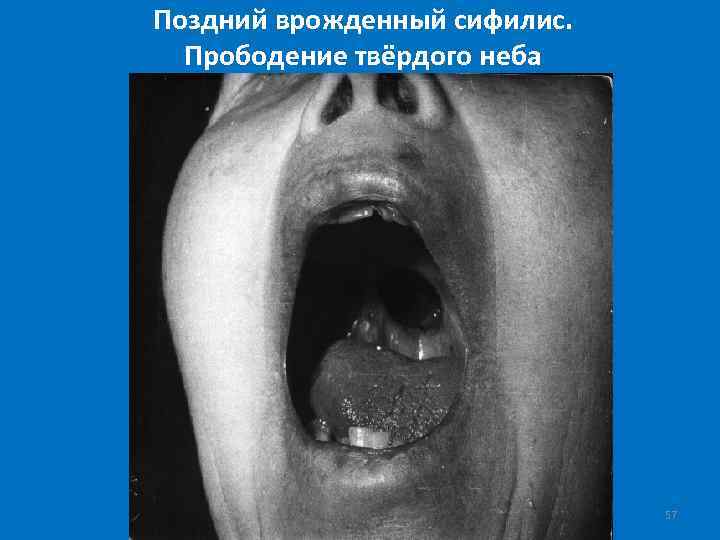

Поздний врожденный сифилис. Прободение твёрдого неба 57